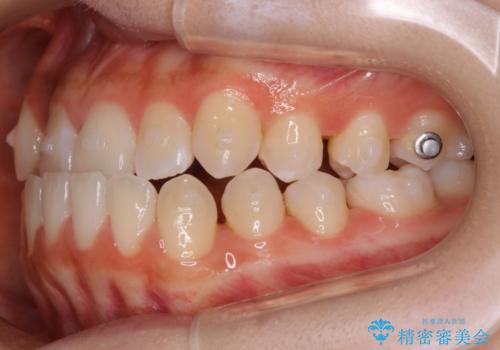

【非抜歯】受け口の改善 10代で始める本格的噛み合わせ治療

- 受け口の改善と前歯のガタつきの治療を主訴にご来院されました。

こちらの患者様の場合、上の前歯のガタつきが原因で口を閉じる際に上下の前歯の先端同士が先に当たってしまい、そこからさらに深く噛み込もうとすると下顎が前にずれていってしまうという、機能性の反対咬合であることが検査の結果わかりました。

そのため、まずは上顎の前歯のガタつきを改善していき、前歯が先に当たってしまうという症状を改善し噛み込む位置を後方の本来の位置に誘導する方法をとりました。